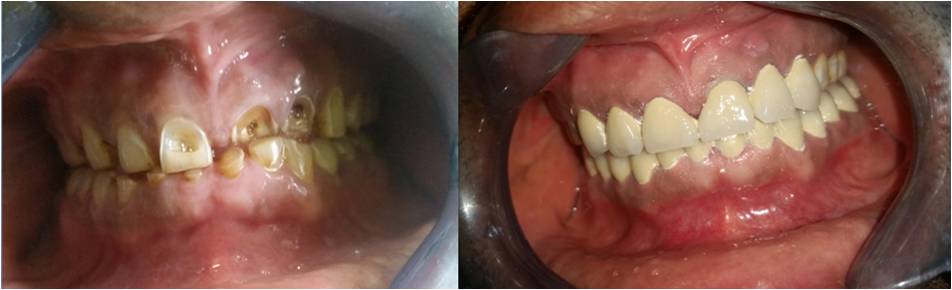

Cosmetic Dentistry